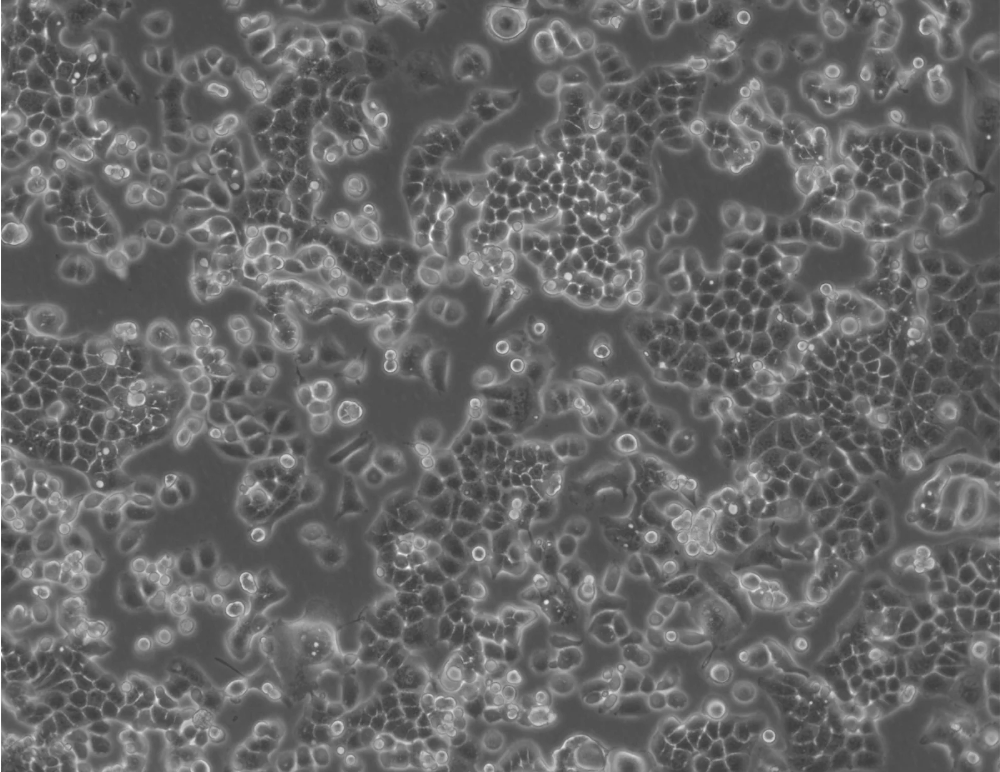

形态 |

上皮细胞 |

生长特征 |

贴壁生长 |

该细胞是H.Kuramoto1968年分离的HEC-1-A细胞亚株。不同於HEC-A-1的是:该亚株在培养第135天到190天之间表现出稳定的生长周期,且重现扁平,与亲本细胞系相比更具铺路石式样。此外主要染色体组是亲本细胞的两倍。 |